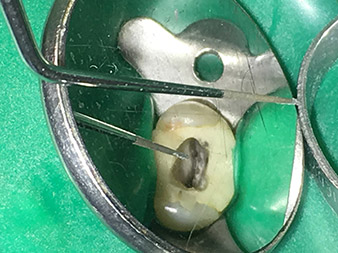

Visual aids such as dental loupes or even better a surgical microscope should be employed for all indications in the canal. In addition, I also think it is important that all the applications in the canal – with the exception of the activation of the rinsing fluid – are performed by specialized colleagues with corresponding experience and the necessary expertise in the field.

The risk of perforations and steps forming in the canal must not be underestimated, as the risk increases the deeper one delves into the canal.

Pictures: Dr. Shahrad Nouraie Ashtiani, Bremen